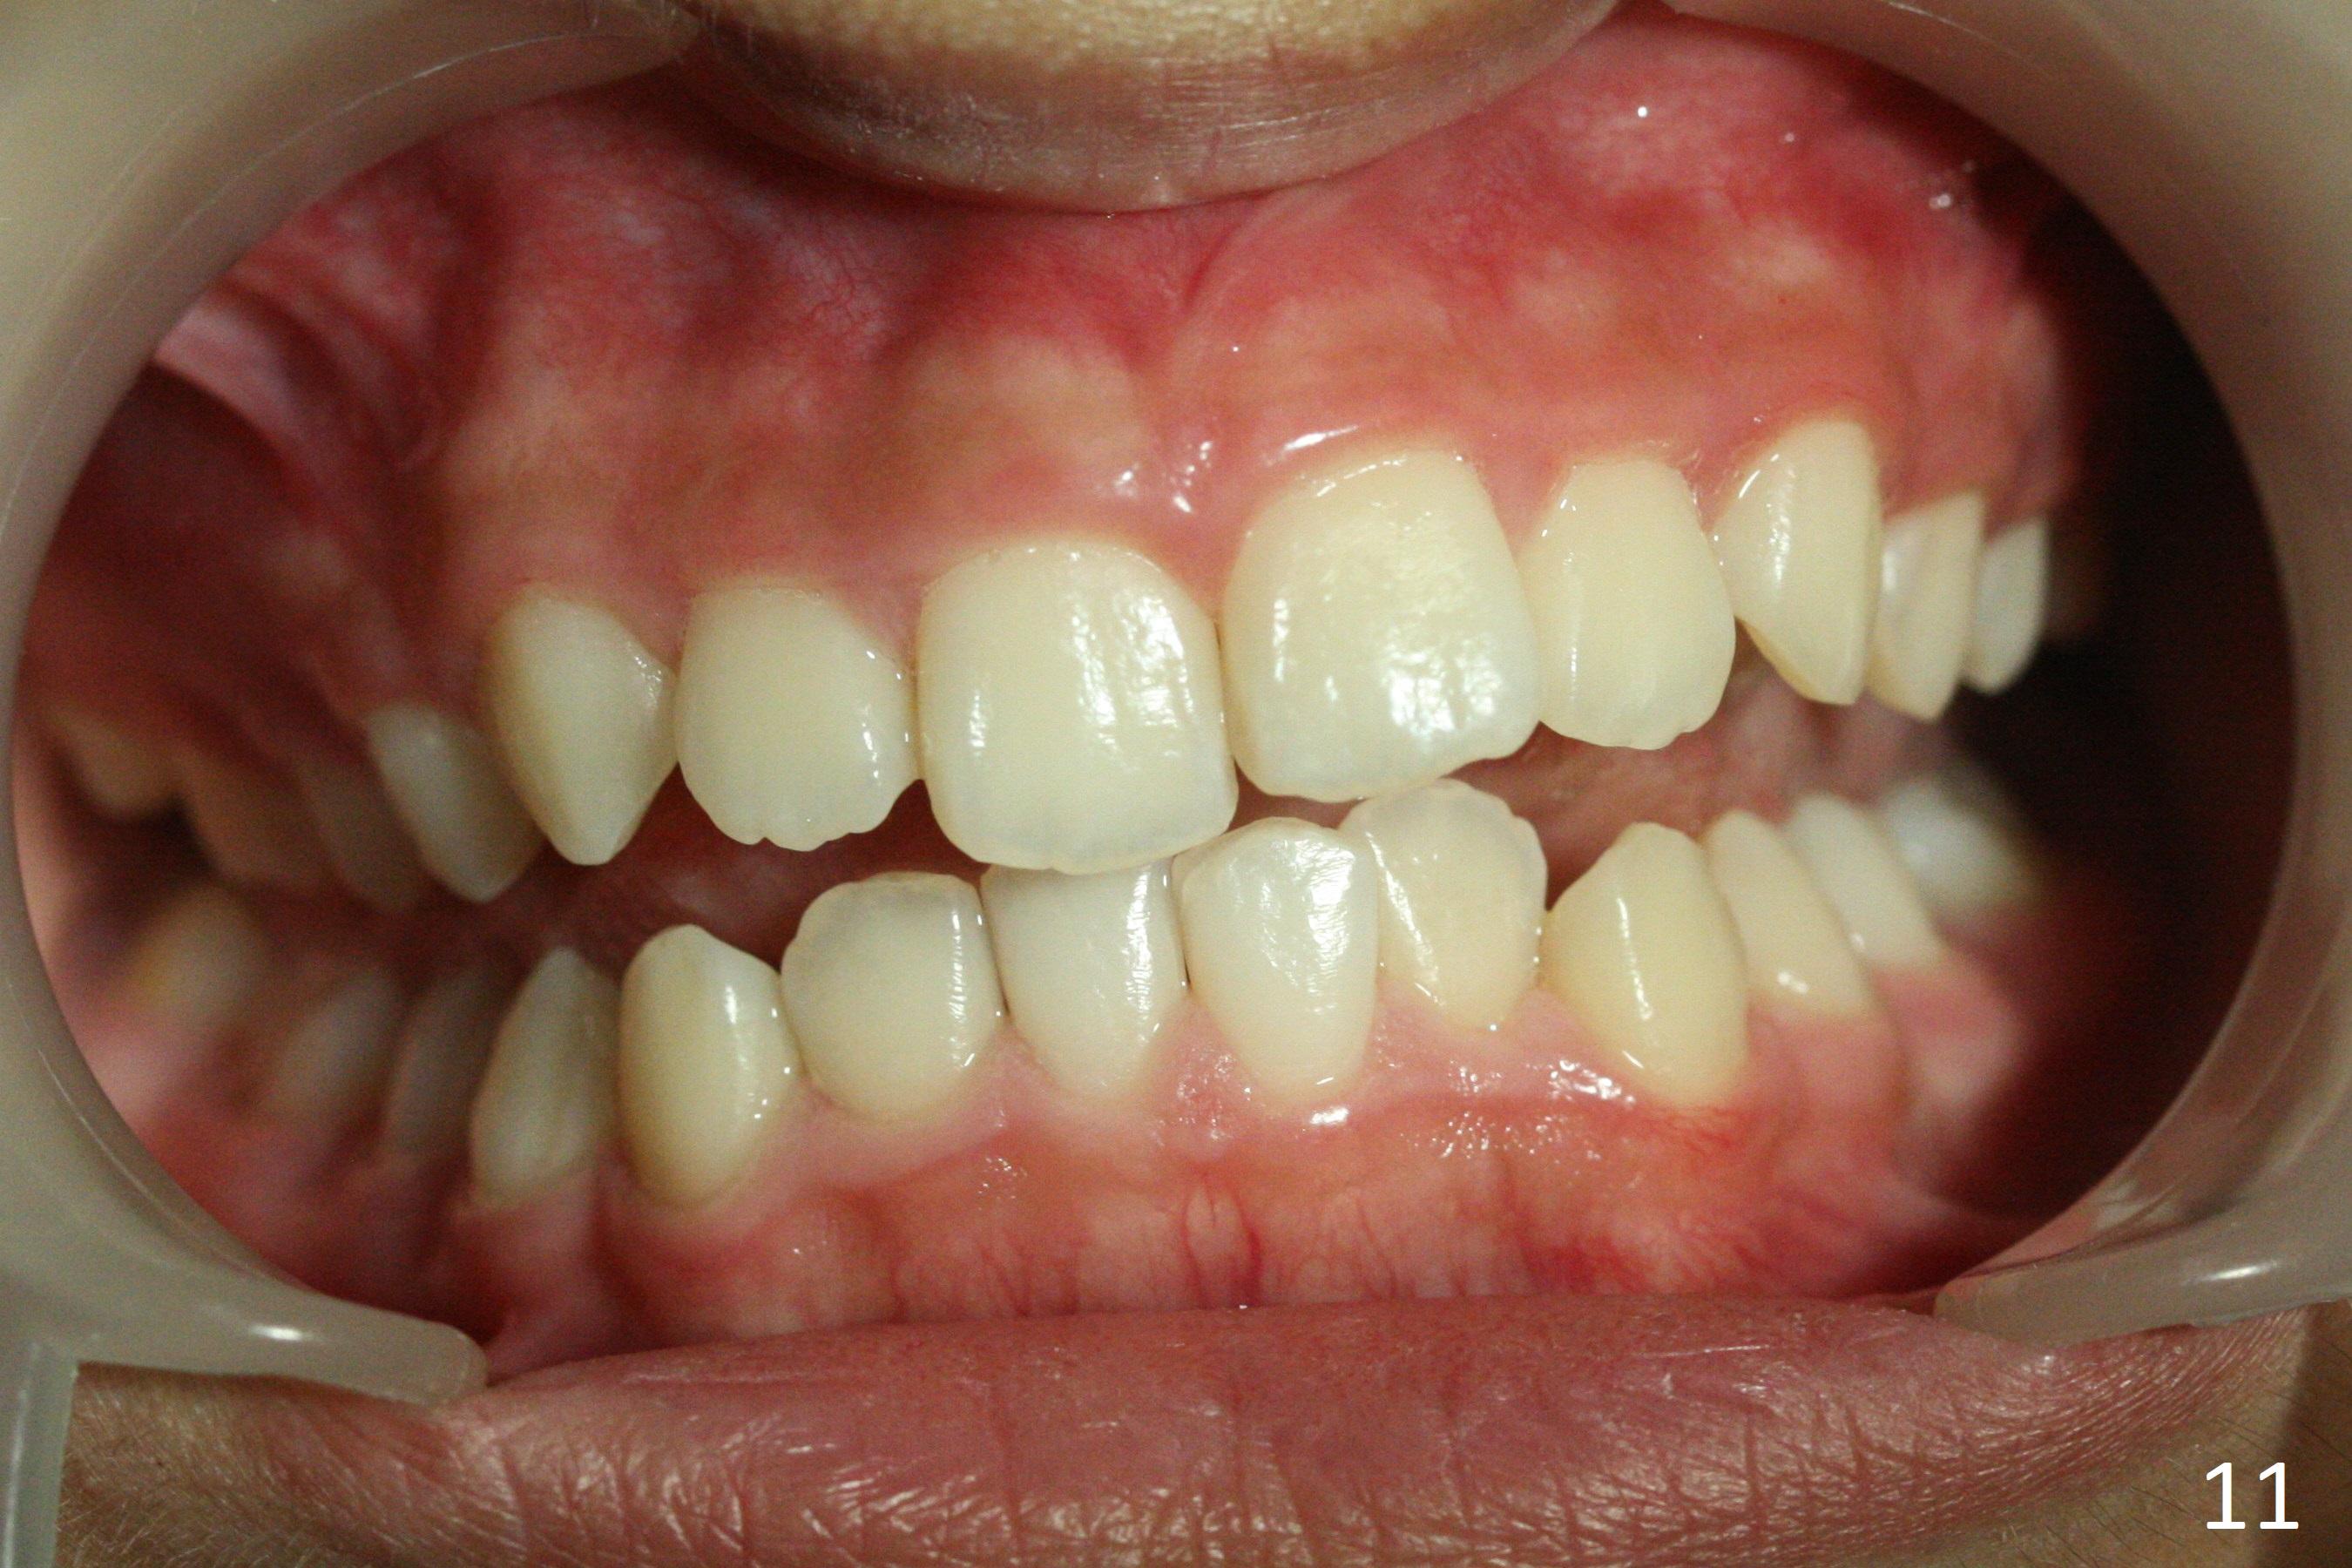

A 12-year-old woman has normal facial profile (Fig.1-6,12) and crowded dentition (7-11). Because of erupting 2nd molars (Fig.10,15), it is difficult to place rubber separators between U6/7. Copper ones are used instead (Fig.15 ^). Crowding and narrow arches (Fig.13,14) may be associated with the enlarged right Inferior Nasal Concha (Fig.15 *).